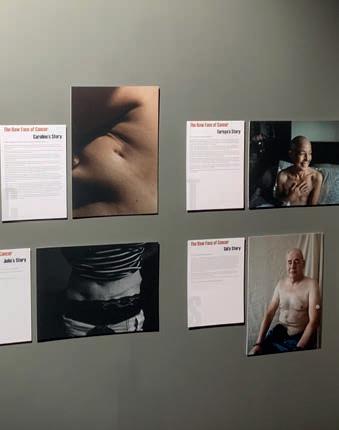

n collaboration with MacMillan Cancer Support, this exhibition hosted in Beecroft’s Community Space is entitled 'The Raw Face of Cancer - Photographs by Mia Davies'. Through photography and personal accounts, the exhibition explores the di erent experiences of 15 individuals a ected by cancer. Mia’s photographs capture the pain of cancer, but are uplifting too. southendmuseums.co.uk/beecroft